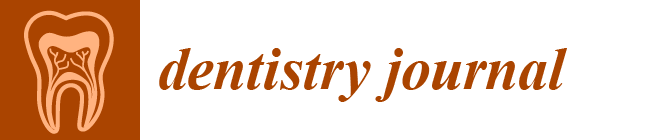

3.1. Applications of AI in Prosthodontics and Implant Dentistry

4.1. Applications of AI in Prosthodontics and Implant Dentistry